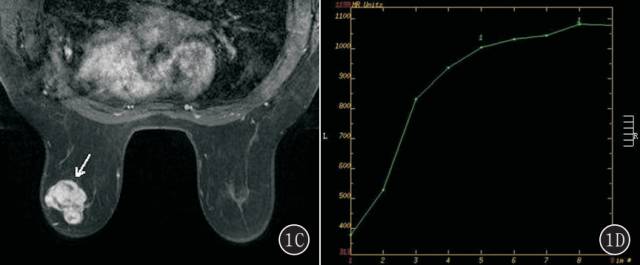

图2A~E 女,54 岁,右侧乳腺单纯型黏液腺癌。 A. T2 WI 右侧乳腺外下象限卵圆形肿块(白箭头),明显高信号,边缘多发细毛刺(黑箭头);B. T1 WI 平扫呈周边环形等信号,中心不均匀低信号(白箭头),边缘多发细毛刺(黑箭头);C. 动态增强呈环形强化(白箭头),强化环厚度不均匀,边缘多发细毛刺(黑箭头);D. 时间-信号强度曲线呈持续型;E. DWI 呈明显高信号(白箭头)